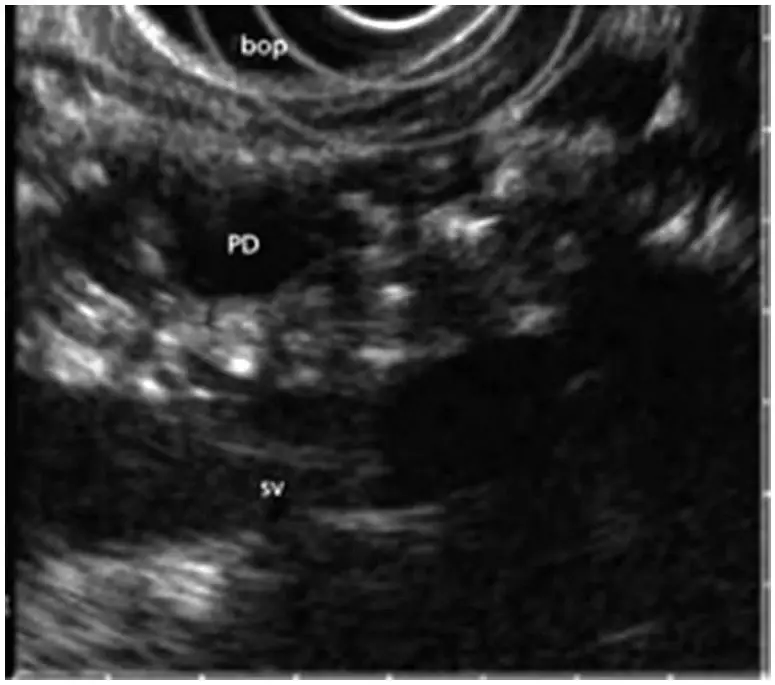

超声内镜(Endoscopic Ultrasound,EUS)是将内镜和超声相结合的消化道检查技术:将微型高频超声探头安置在内镜顶端,当内镜插入消化道后,在内镜直接观察消化道病变的同时,利用内镜下的超声实时扫描消化道及周围结构。

相比于常规的腹部B超,超声内镜技术探查胰腺具有天然的优势。因利用消化道自然腔道进行探查(胃壁紧邻胰腺),可有效避开腹壁脂肪、胃肠道气体等的干扰,而且能了解病变深度、起源,此外,还可通过穿刺、引流、注射及粒子种植等方法进行相关治疗。

超声内镜对于胰腺先天性发育异常的诊断准确率明显高于常规影像手段(95%以上),弥补了对于胰腺发育异常缺乏诊断工具的缺憾,并通过进一步胰管支架或胰管引流,有效缓解急性胰腺炎,避免再发;